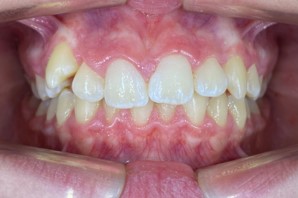

This case showcases an innovative approach to correcting lower jaw retrusion in growing patients using the Angel Aligner A6. The system combines orthopedic and orthodontic treatment into a single protocol, allowing simultaneous advancement of the lower jaw and alignment of teeth. With digital planning and aesthetic aligners, the treatment is both effective and comfortable for the patient. This case was managed by Dr. Giacomo Scuzzo